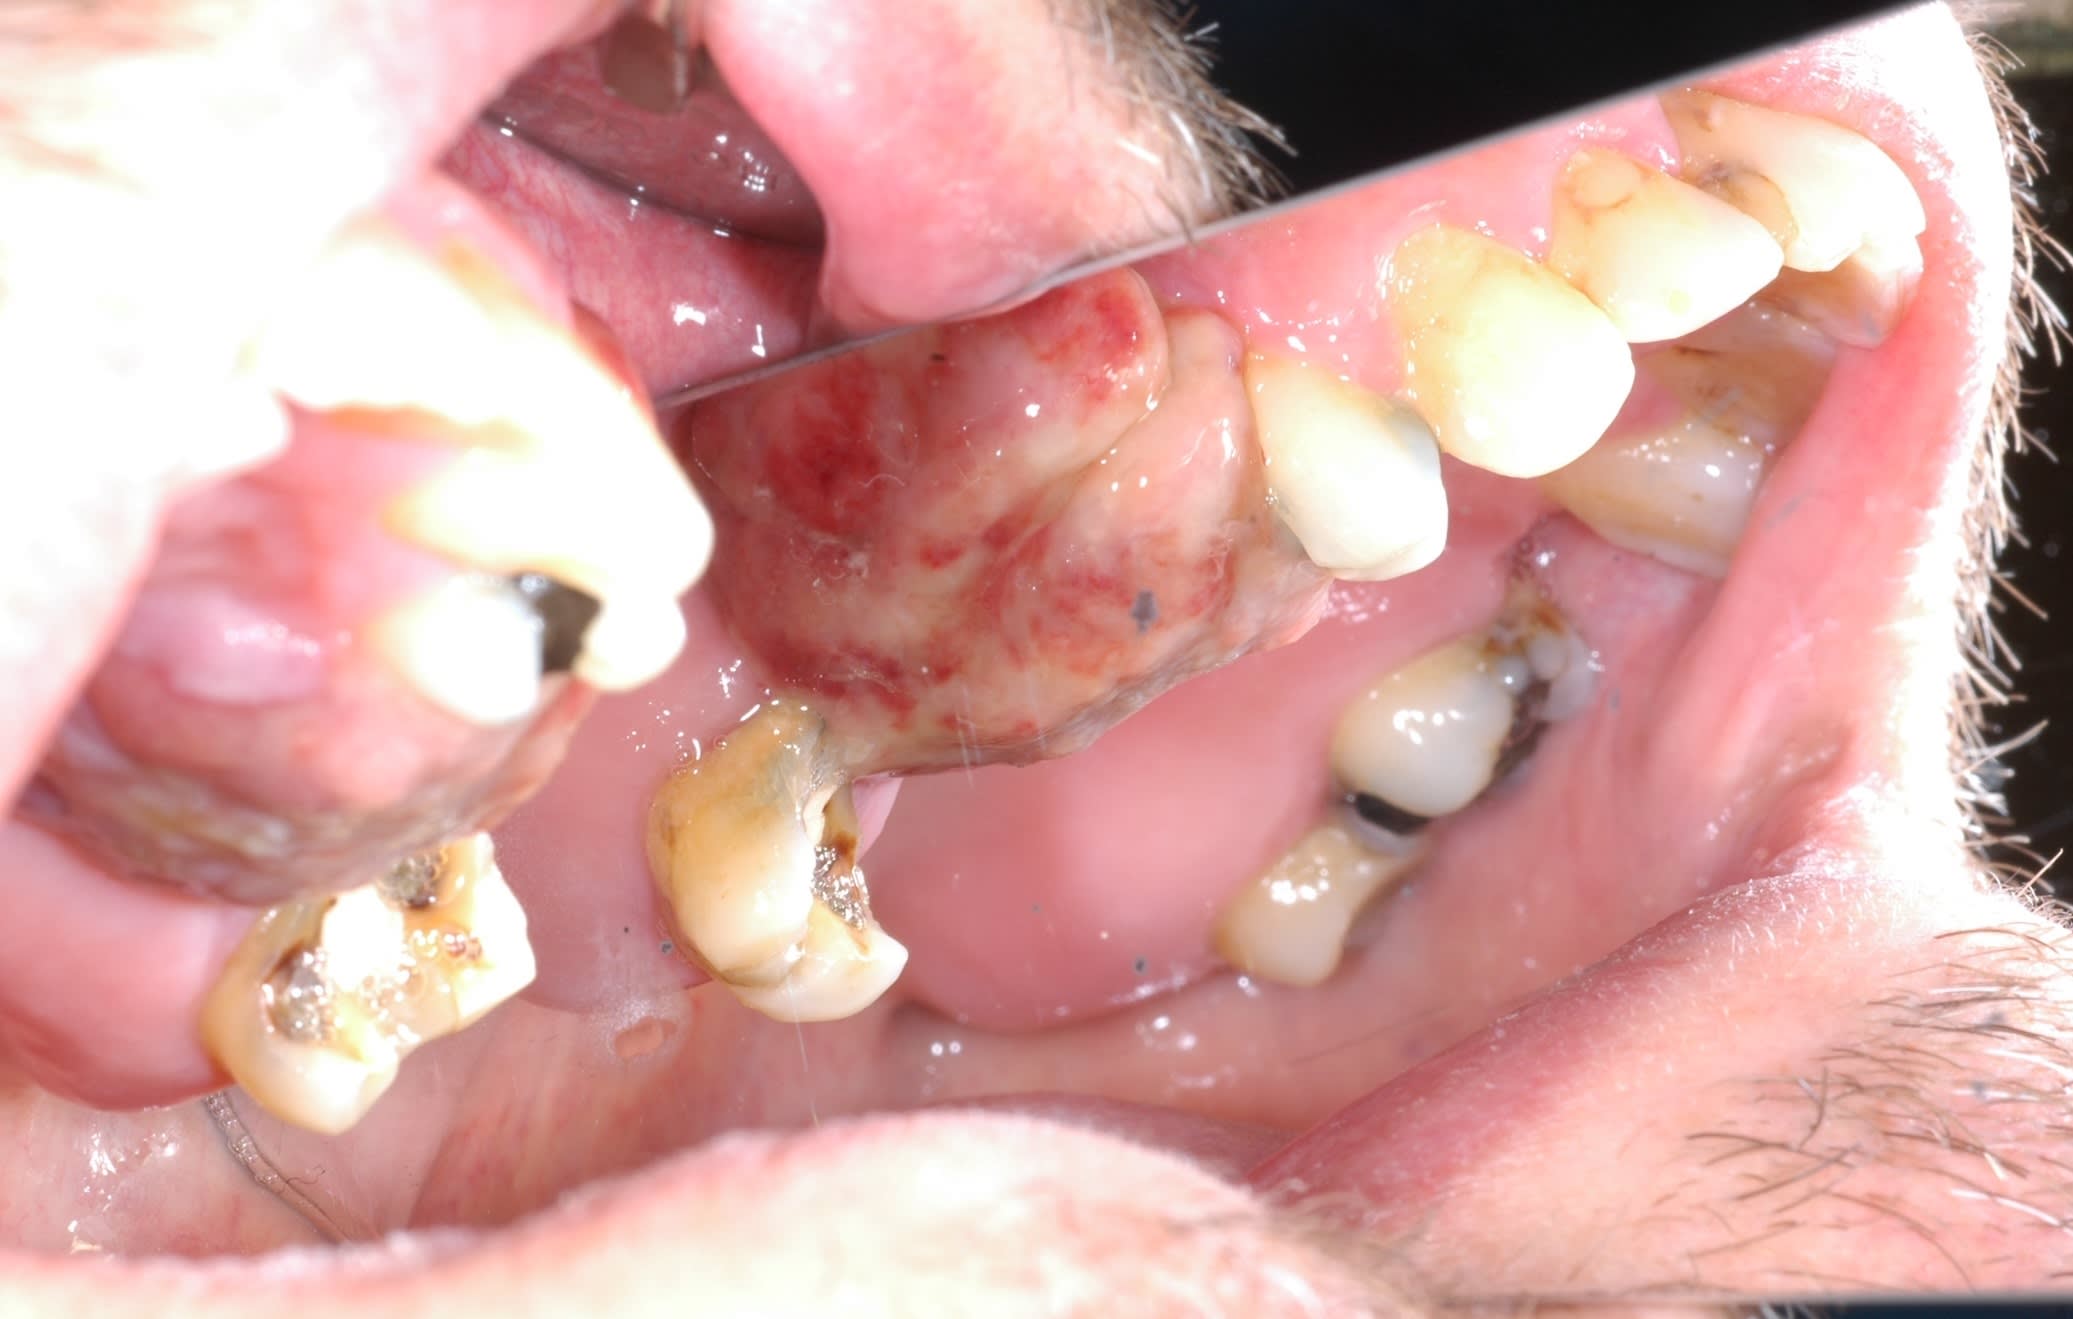

En continuant avec les envahissements de sinus.

Une idee de diagnostic? Evolution depuis 3 mois, facilement mobilisable, saignement a palpation, qui a envahit le sinus.

Patient a aucune douleur. Pas d adenopathies peripheriques.

En bonus un autre probleme de sinus...

C est un Granulome central a cellules geantes a progression lente. ( Image clinique tres proche carcinome epidermoide)

Traitement envisage est injection de biphosphonates( Denosumab) pour reduire la lesion. Cela permettrait d eviter une resection en bloc type hemimaxillectomie et reconstruction par fibula.